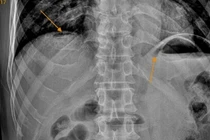

Người đàn ông 61 tuổi đến bệnh viện khám trong tình trạng đau bụng đột ngột dữ dội như dao đâm vùng thượng vị, sau đau lan khắp ổ bụng,... Các bác sĩ chẩn đoán bệnh nhân bị viêm phúc mạc do thủng tạng rỗng.